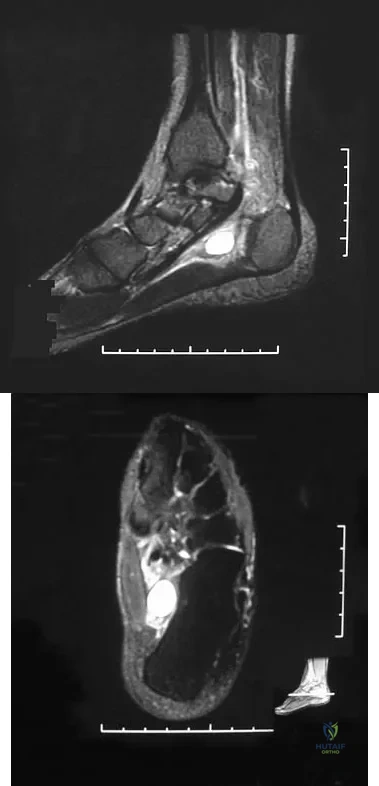

Question 72

A 40-year-old man has a painless mass around his left ankle. He notes minimal growth over the past year. An MRI scan is shown in Figure 73a, and biopsy specimens are shown in Figures 73b and 73c. What is the most likely diagnosis?

Explanation